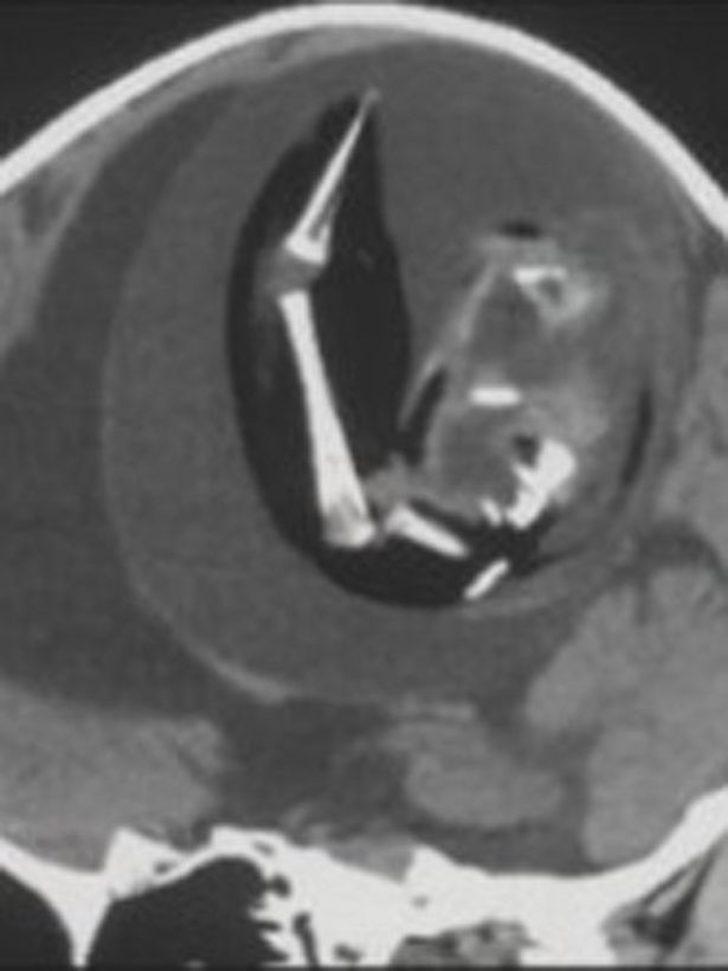

Çin’deki Feudan Üniversitesi’nde ilginç bir tıbbi vaka yaşandı. İsmi açıklanmayan 1 yaşındaki kız çocuğunun doğmamış ikizinin anne karnındayken kafasının içine girerek büyümeye devam ettiği belirlendi. Fetüs içinde fetüs olarak bilinen bu tıbbi durumda 1 yaşındaki kız çocuğunun kafasının içindeki ikizinin fetüsü büyümeye devam etti. Fetüsün üst uzuvları, kemikleri ve tırnakları gelişti. Durum BT taramalarında tespit edildi.

Kızın doğumundan yaklaşık 1 yıl boyunca fark edilmeyen fetüs hayatta kalan ikizi ebeveynlerinin büyük kafatası ve motor becerilerindeki problemler nedeniyle hastaneye götürmesiyle ortaya çıktı. Fetüs, kardeşiyle kan akışını paylaştığı için kafatasının içinde bir yıl hayatta kalmayı başardı, ancak sonunda ameliyatla alındı.